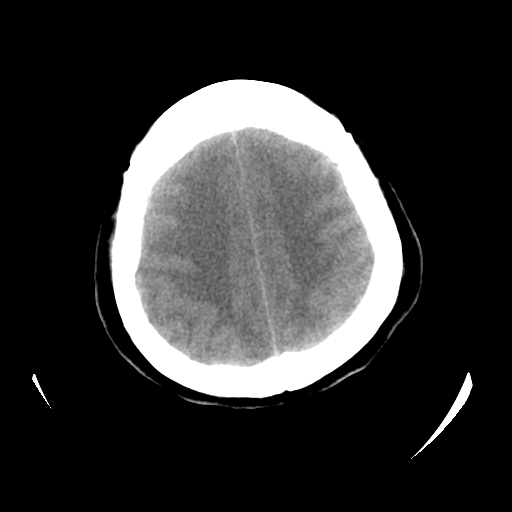

女,53岁,发现昏迷1天,血压不高,有精神病史。临床诊断:脑梗死?

ct诊断:1、双侧基底节区对称性脑梗塞。

2、双侧额叶、枕叶广泛密度减低,考虑缺血梗塞可能性大。

3、脑池小,脑沟浅,提示颅内高压。

测左枕叶白质ct值 约22hu 。请各位老师给出恬当诊断。

征象:病变呈对称性分布于双侧大脑半球,累及范围广泛,白质较灰质密度减低更为明显;脑沟变浅,脑池变窄;